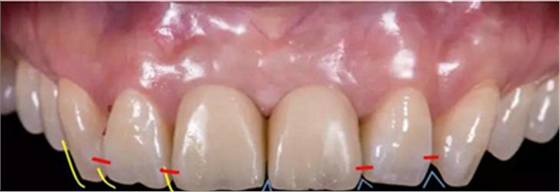

患者33歲,女性,主訴4個(gè)月前因外傷拔除上11、21牙,未行活動(dòng),固定義齒修復(fù),現(xiàn)因影響美觀要求種植修復(fù)。11,21牙缺失,缺牙區(qū)牙齦狀況良好,無(wú)潰瘍紅腫,厚齦型,口腔衛(wèi)生較好,無(wú)明顯牙齦退縮。

1、中切牙長(zhǎng)度10~11mm,寬長(zhǎng)比75%~80%,比側(cè)切牙寬2~3mm,比尖牙寬1~1.5mm。

2、中切牙可以與尖牙頸緣同高,理想的側(cè)切牙齦緣位置應(yīng)低于中切牙0.5~2mm。

技師獲得模型后,行DSD設(shè)計(jì),根據(jù)患者口內(nèi)情況、咬合關(guān)系及患者意愿進(jìn)行牙齒形態(tài)調(diào)整。根據(jù)DSD設(shè)計(jì)進(jìn)行診斷蠟型制作。制作過(guò)程中需充分考慮影響美學(xué)重建修復(fù)的因素,包括中切牙寬長(zhǎng)比、牙齒形態(tài)、牙齦曲線、切緣弧度(咬合關(guān)系)等。

可以觀察到鄰牙形態(tài)為尖圓形,為了獲得一個(gè)美觀效果且能關(guān)閉黑三角,牙齒形態(tài)由鄰牙的尖圓形改為方圓形。